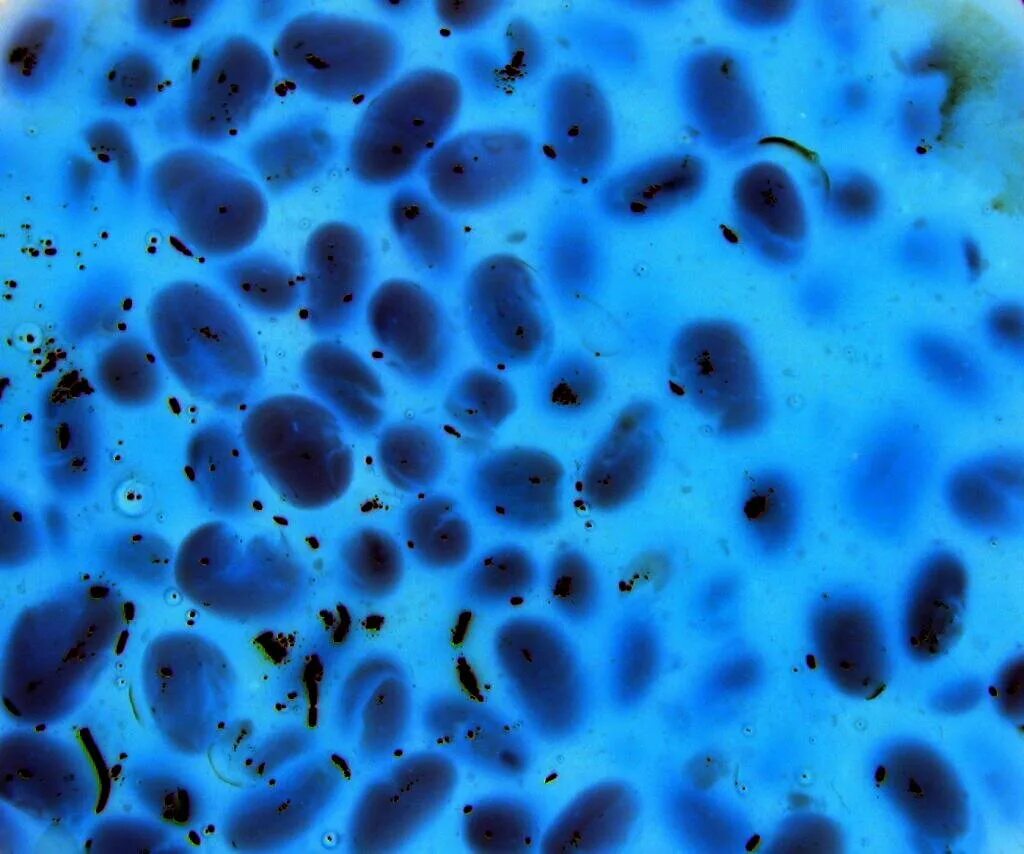

Микроскоп чтобы увидеть микробов